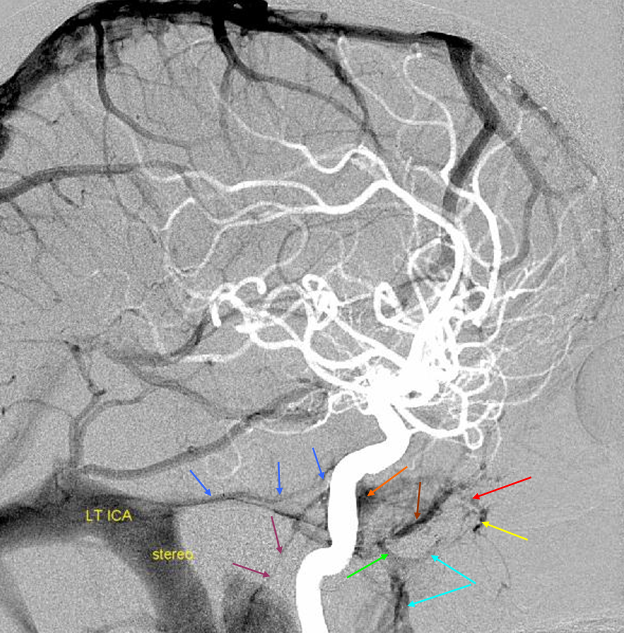

5) Clival venous plexus down to foramen magnum region, and from there into jugular veins or marginal sinus. A neat way of projecting arterial phase as a mask for venous phase to demonstrate carotid artery relationship to the cavernous sinus. Many tributaries and egress routes of the cavernous sinus are visible.

Stereo of the same

Stereo of the same